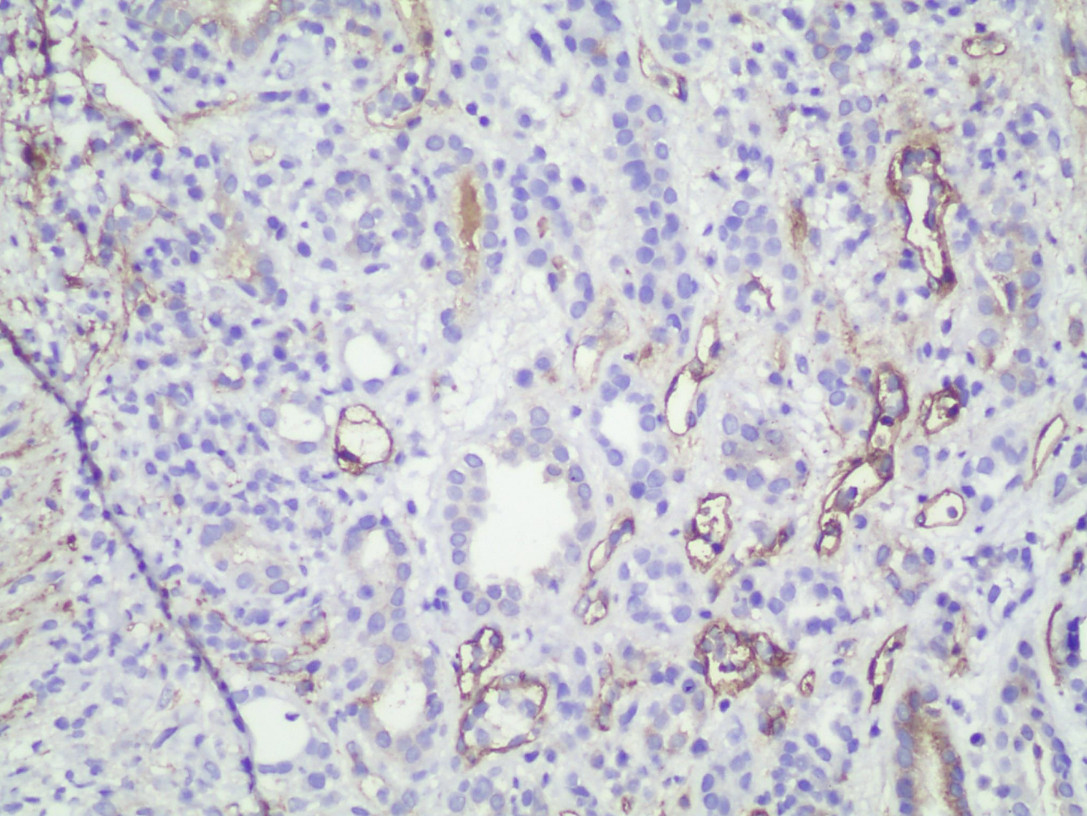

Masculino de 30 años con enfermedad renal crónica terminal de causa desconocida, recibió en 2015 trasplante renal de donador cadavérico. Ingresó con deterioro de la función renal, por lo que toman biopsia de injerto.

Rechazo a injerto renal